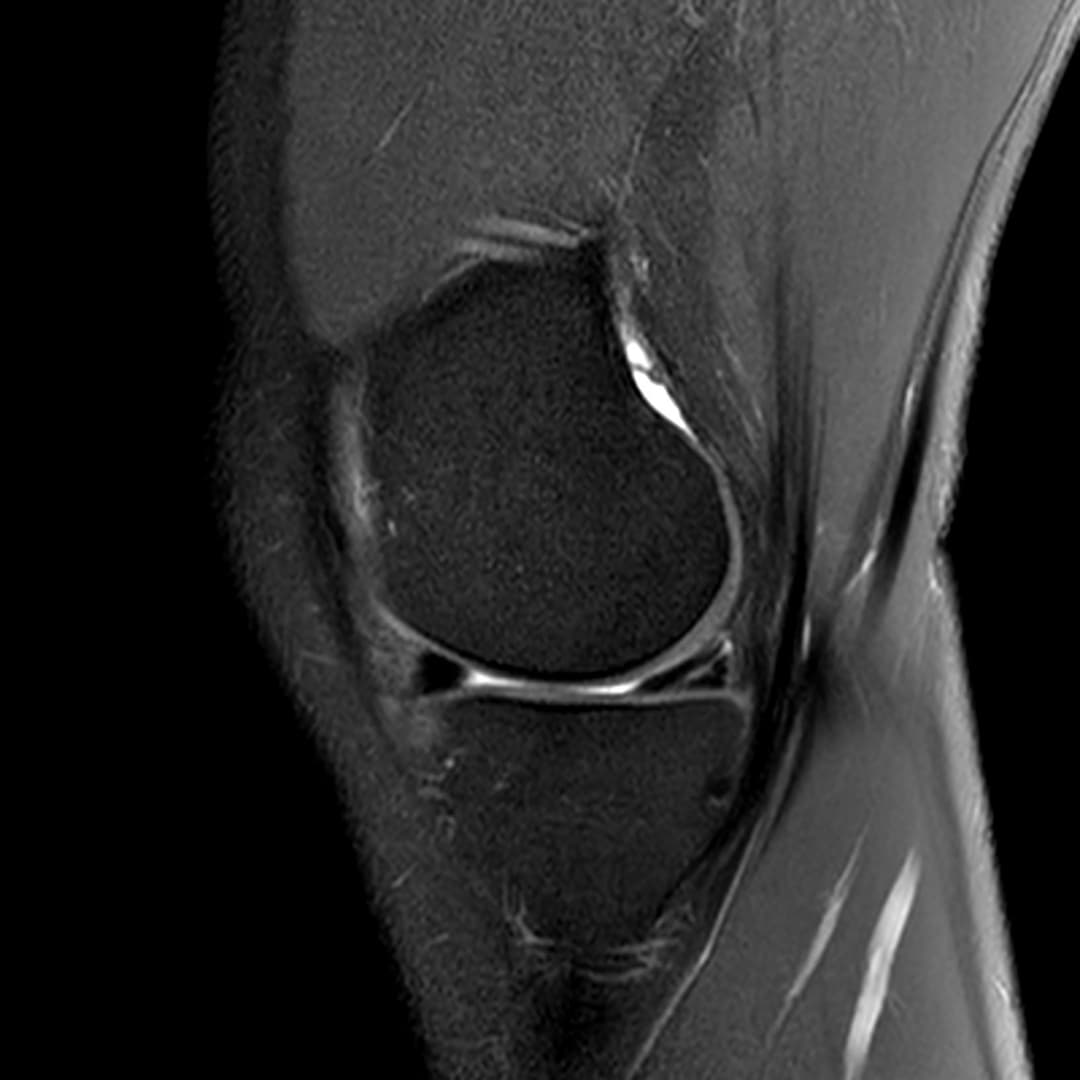

Fissure de grade 3 du segment moyen du ménisque médial.